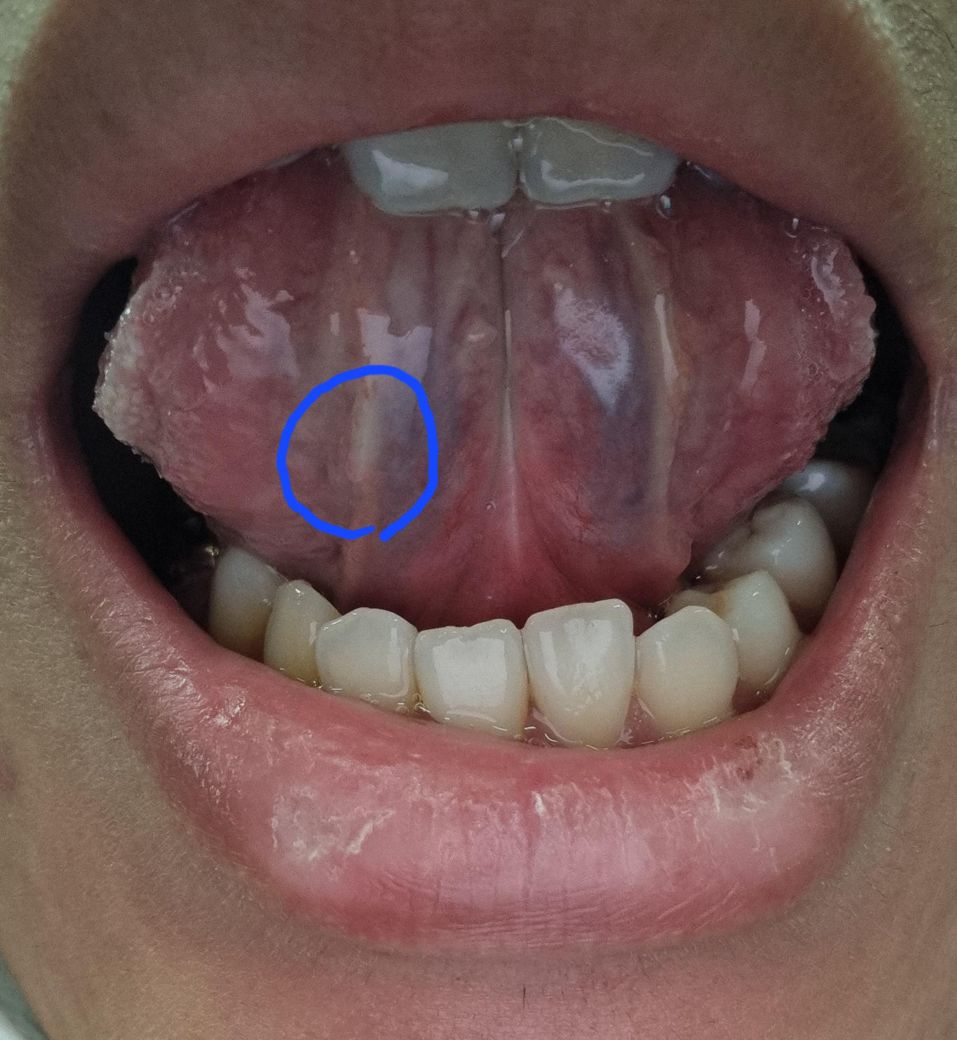

혀 밑 하얗게 염증이 생겼는데 구내염일까요?

입안쪽은 꼬매놨고 혹시 꼬매놓은거 때문에 염증이 생겼을 수도 있을까요? 최근에 피곤해서 면역력도 떨어지고 입안에 상처가 꽤 나서 다른부위에도 꼬매고 그래서 항생제.진통제도 꽤 오래먹고 있습니다. 혀밑 염증때문에 말할때도 아랫니에 걸려 통증이 있고 밥먹을때도 있습니다. 혓바늘 약을 바르면 될까요?

• 1번 째 사진